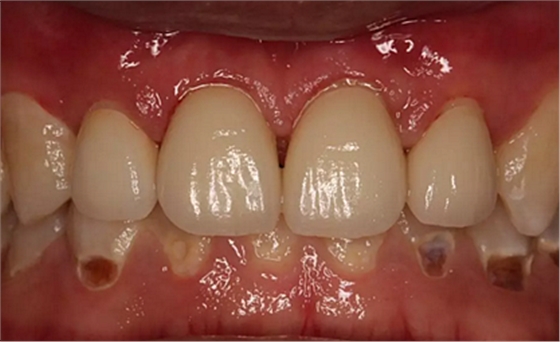

第5次復(fù)診的時(shí)候,終于讓我們4個(gè)兄弟恢復(fù)了正常的容顏。

現(xiàn)在剩下的任務(wù)就是為我其他的兄弟姐妹們治療了。需要做根管的做根管,需要做冠的做冠,需要樹脂充填的做樹脂充填。前前后后主人帶我們進(jìn)行了12次的復(fù)診,歷時(shí)6個(gè)月,現(xiàn)在的我們是這樣的